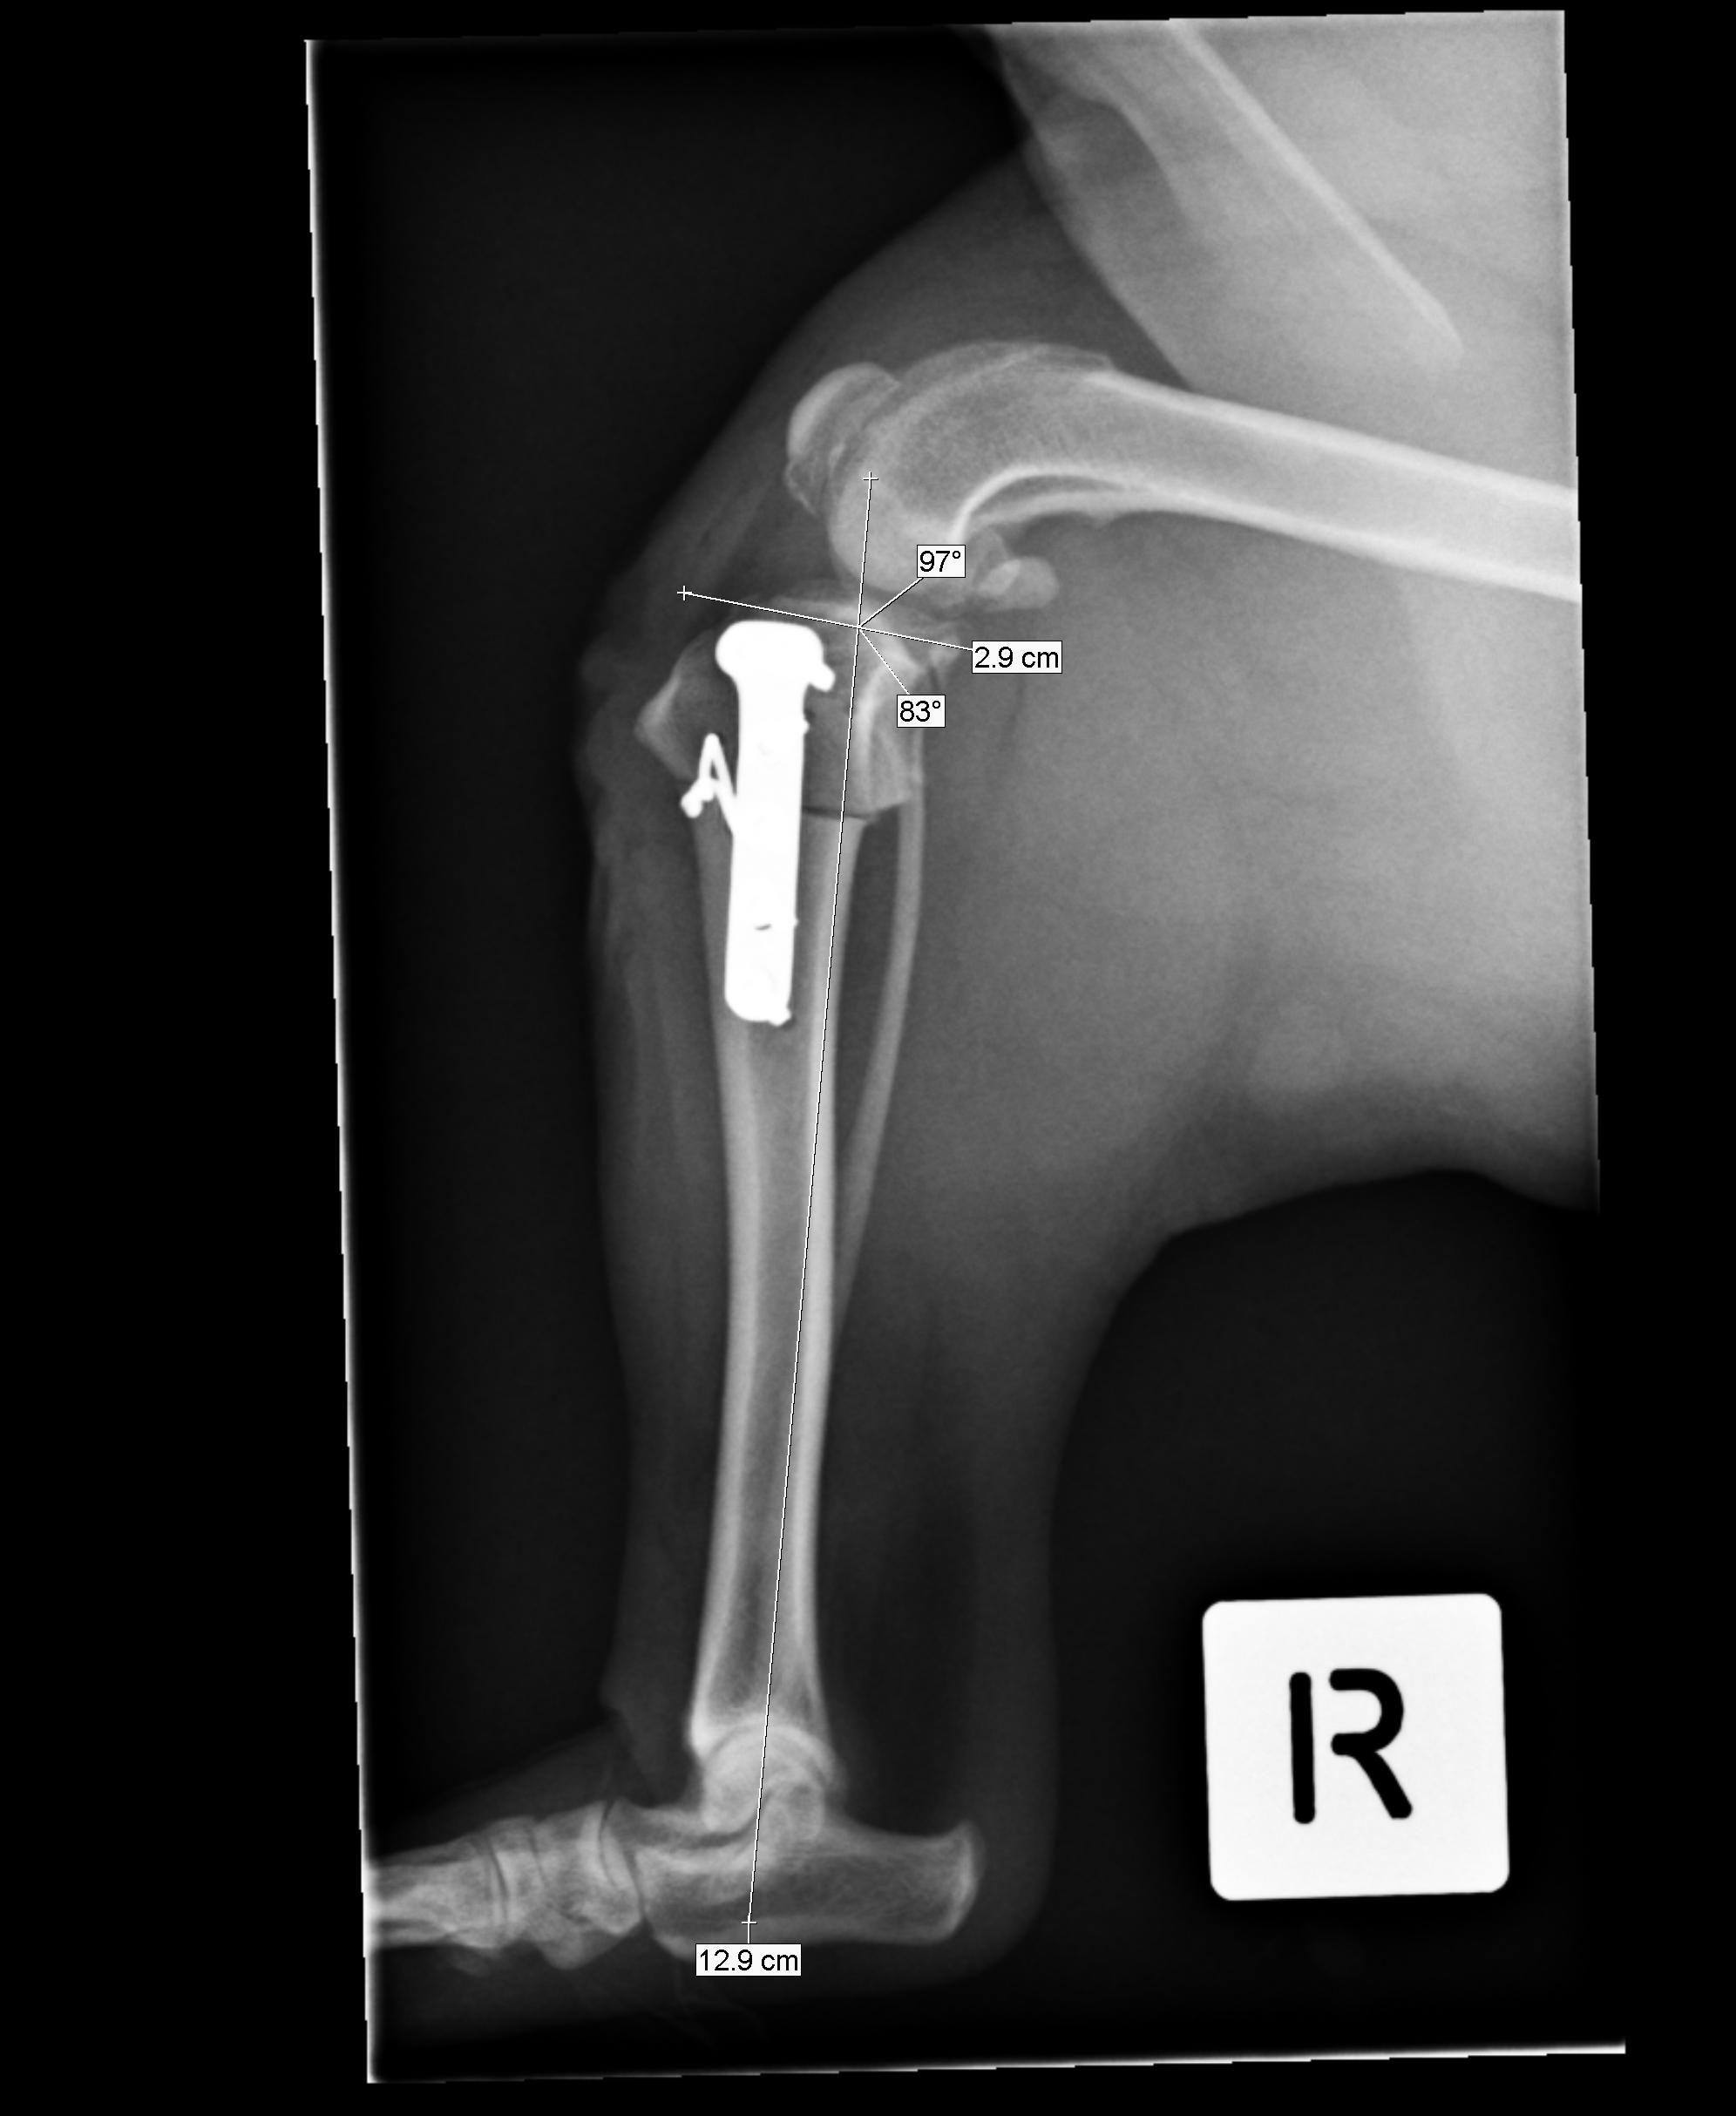

Figure 6 from Meniscal injury in dogs with cranial cruciate ligament rupture. Semantic Scholar. Causes and Symptoms of Dog Meniscus Tear After TPLO. The meniscus is a piece of connective tissue that sits within a dog's knee, dividing the femur and the tibia